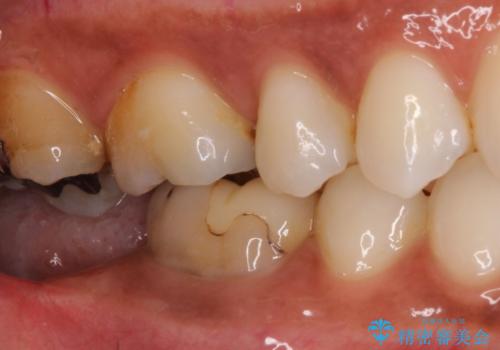

- 奥歯が痛いことを主訴に来院されました。

根管治療を行なったのちオールセラミッククラウンにて修復補綴を行いました。

根管治療歯は破折を防止するために速やかに被せ物の治療を提案いたします。